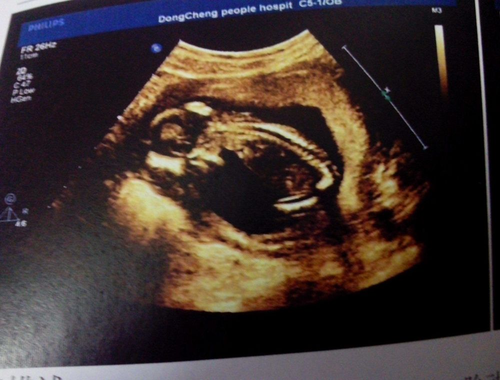

这些母亲在怀孕的时候并没有做过完整的孕检,有些人抱着侥幸的心理,认为做孕检是一种比较浪费时间与金钱的行为,所以在怀孕期间从未关注过自己的身体状况,以及胎儿的健康情况。等到孩子出生后,才后悔莫及。